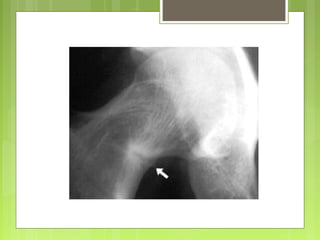

A nivel de la cadera: las localizaciones más frecuentes son próximas a los

cartílagos de crecimiento